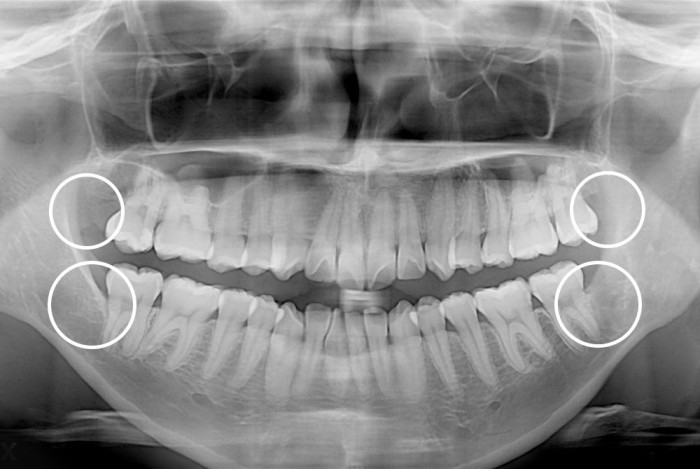

[사랑니] 매복 사랑니 발치

치료전 : 2018-01-30